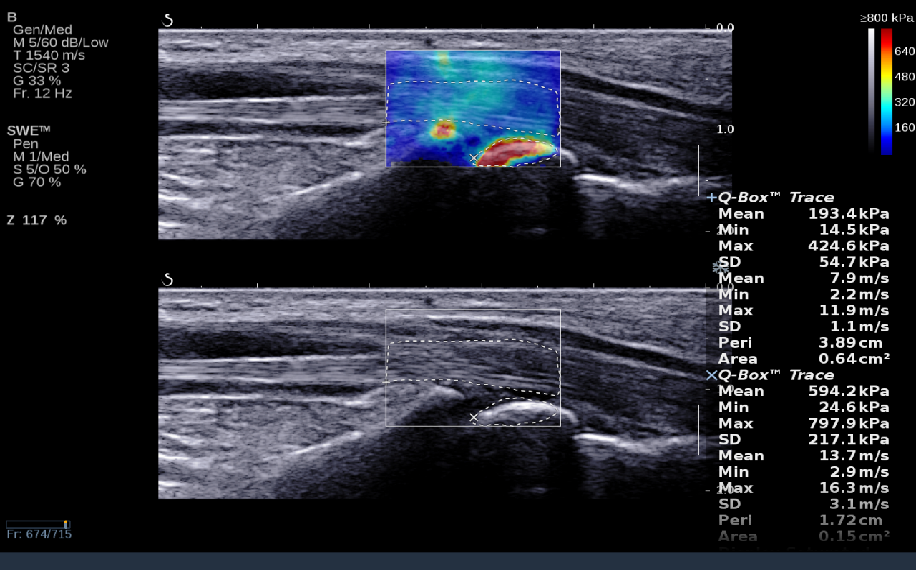

RTSWE实时剪切波弹性成像

Ø探头发射激励脉冲进行多点动态聚焦,利用马赫圆锥原理,形成大量的剪切波信号Ø颜色的变化与剪切波的速度相关,可直接体现肌肉肌腱等组织硬度值Ø实时、全幅、全定量

鉴别诊断、精准分级、定量评价、穿刺引导、疗效评估、随访观察